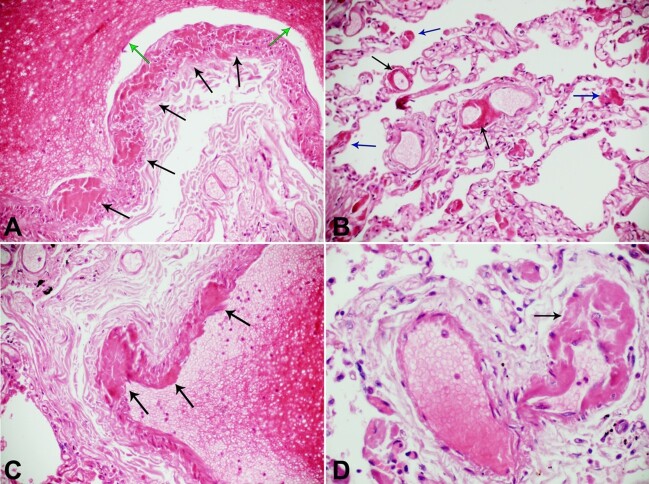

The vasa vasorum of the large pulmonary vessels is involved in the pathology of COVID-19. This specialized microvasculature plays a major role in the biology and pathology of the pulmonary vessel walls. We have evidence that thrombosis of the vasa vasorum of the large and medium-sized pulmonary vessels during severe COVID-19 causes ischemia and subsequent death of the pulmonary vasculature endothelium. Subsequent release of thrombi from the vasa interna into the pulmonary circulation and pulmonary embolism generated at the ischemic pulmonary vascular endothelium site, are the central pathophysiological mechanisms in COVID-19 responsible for pulmonary thromboembolism. The thrombosis of the vasa vasorum of the large and medium-sized pulmonary vessels is an internal event leading to pulmonary thromboembolism in COVID-19.